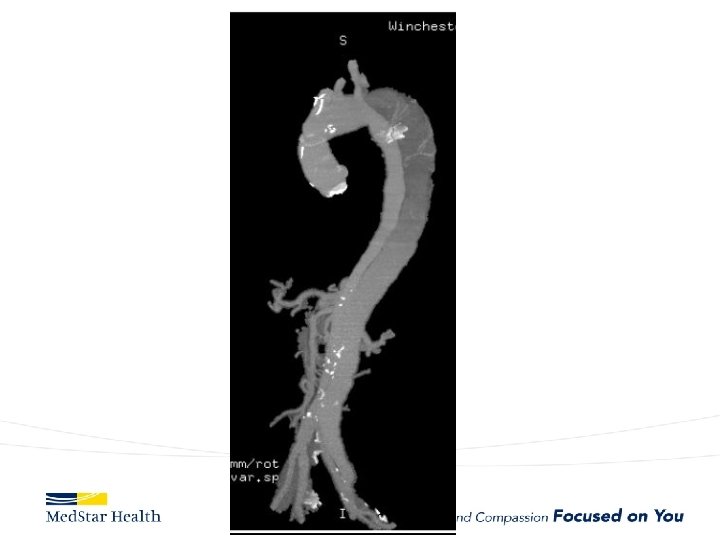

Acute Type B Aortic Dissection • Incidence: 2. 6 -3. 5 per 100, 000 patient-year • Uncomplicated • Complicated – – Malperfusion Rupture Unremitting Pain Uncontrolled HTN

Type B Dissection Complicated Uncomplicated Risk TEVAR age, comorbidities Extreme Low Medical Management False Lumen Small, Thrombosed Medical Management Patent/Large(>22 mm), Total Aorta >40 mm TEVAR/adjuncts

Aneurysms • Descending – Obvious first choice assuming anatomically favorable • Ascending – IDE, Off label in high risk patient • Arch – Available in Europe, Under Trial in US • Thoraco – Available in Europe, Under Trial in US